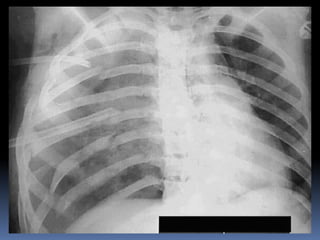

Abnormal Findings Un equalityof chest movement Dullness on percussion Decrease air entry Tachypenic heamothorax chest tube